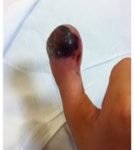

A 12-year-old male presented to the emergency department with right thumb pain and a mass for four months (see images). He denied fevers, chills, change in appetite, or fatigue. He noted that the lesion was growing and “bleeds easily if bumped.” He denied any trauma to the thumb, except “hitting it” months ago while in football practice.

Magnetic resonance imaging (MRI) showed an “expansile, destructive solid and cystic mass with aggressive…characteristics…” (see images). Tissue biopsy confirmed a giant cell tumor arising from the bone. The patient underwent a debulking procedure, and later a distal amputation. Follow-up on pathology showed negative margins.